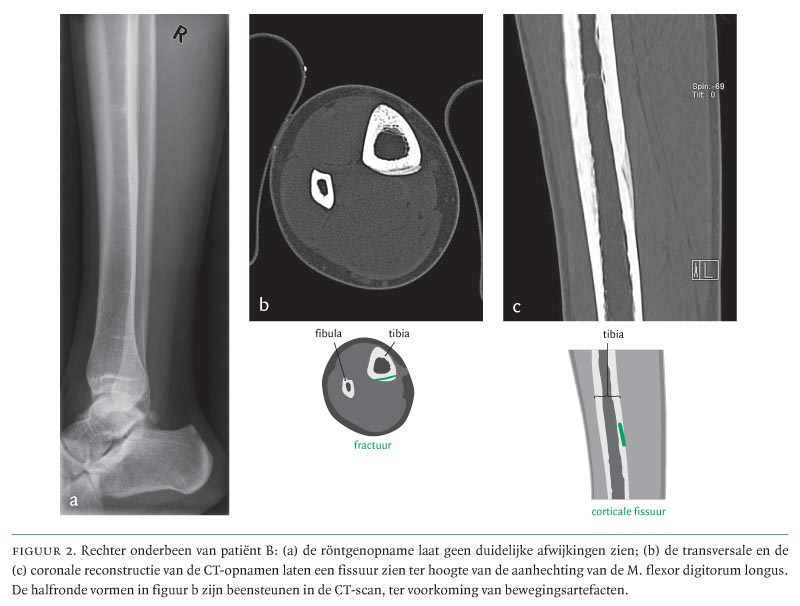

Drie Tevoren Gezonde Personen Met Een Vermoeidheidsfractuur Nederlands Tijdschrift Voor Geneeskunde